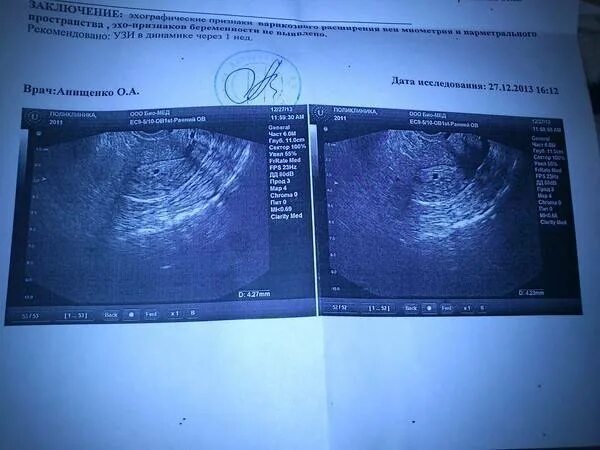

Тест показал а узи нет